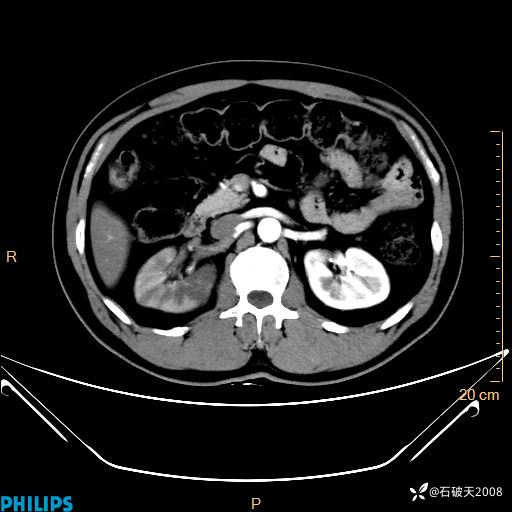

冠状位